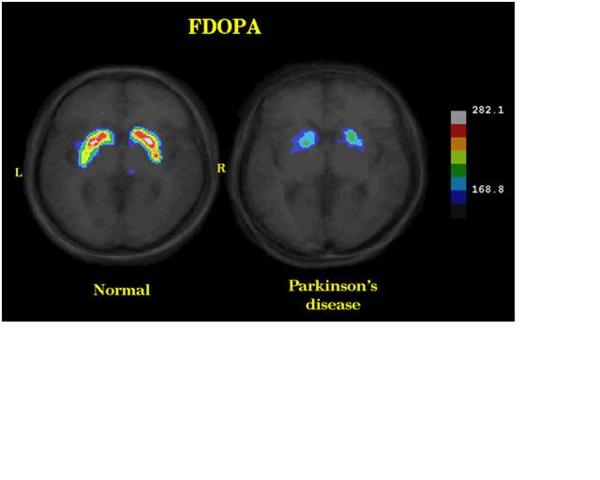

診斷方式: 巴金森氏症之診斷可分為三種階段: 一、 依據臨床症狀:依據之前敘述的臨床症狀包括顫抖、肢體僵直或行動遲緩作為診斷的依據,然而僅依此作診斷,即使是具有經驗的醫師亦有20%的錯誤機率,此乃由於...